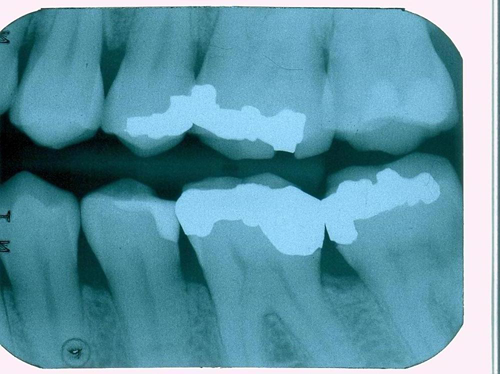

Fig. 5

We scanned the margins of the maxillary first molar with The Canary System and found Canary Numbers ranging from 47 to 76 around the margins of the amalgam (Fig. 5). Removal of the amalgam restoration confirmed the presence of caries in both areas (Fig. 6).